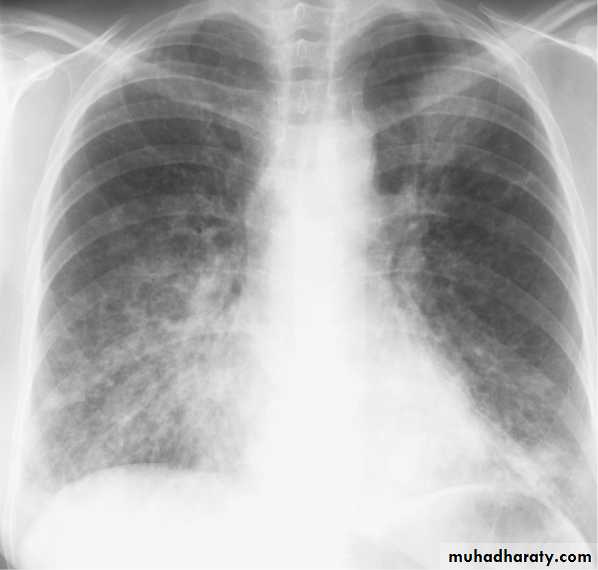

BRONCHOPNEUMONIA

Mycoplasma pneumonia. A 35 year old man presents with nonproductive cough and fever